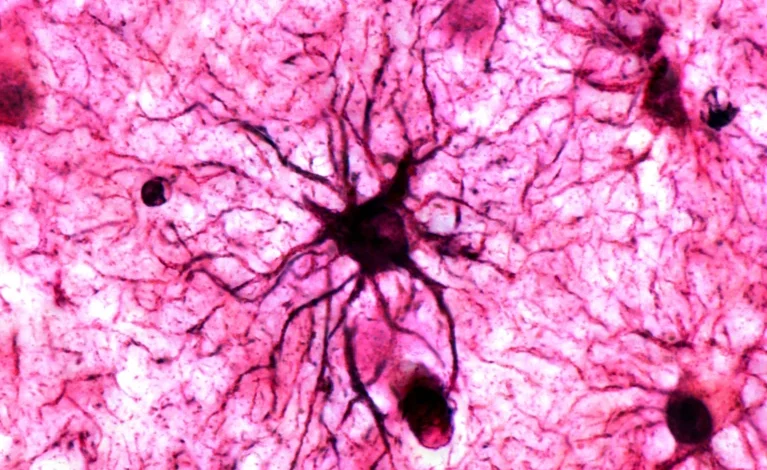

به گزارش پایگاه علمی خبری دانه، وبسایت علمی Nature به تازگی گزارش مختصری از شیوه ثیت خاطرات در مغز انسان منتشر کرده است که در آن شرح میدهد آستروسیتها نقشی فعالتر از آنچه پیشتر تصور میشد در تثبیت خاطرات دارند.

“تا پیش از این، تصور میشد آستروسیتها تنها نقش حمایتی از نورونها را بر عهده دارند و به ایجاد ردهای فیزیکی حافظه در مغز کمک میکنند. اما این پژوهش نشان داد که آنها نقشی بسیار فعالتر ایفا میکنند — حتی میتوانند به طور مستقیم با تجربههای عاطفی تکرارشونده تحریک شوند. پژوهشگران پیشنهاد میکنند این سلولها میتوانند هدفی تازه برای درمان اختلالات حافظه، مانند PTSD (اختلال استرس پس از سانحه) و آلزایمر باشند.”

این پژوهشگر و همکارانش روی پرسش تثبیت حافظه تمرکز کردند؛ اینکه چطور یک خاطره کوتاهمدت در مغز ماندگار میشود. پژوهشهای قبلی ردهای فیزیکی خاطرات را در شبکههای نورونی بخشهایی از مغز همچون هیپوکامپ و آمیگدالا شناسایی کرده بودند. اما مشخص نبود این “اِنگرامها” پس از مواجههی مکرر با یک محرک چگونه به خاطرات پایدار بدل میشوند.

برای مطالعه دقیقتر، پژوهشگران روشی ابداع کردند تا الگوهای فعالسازی آستروسیتها را در سراسر مغز یک موش، هنگام انجام یک تکلیف حافظه، اندازهگیری کنند. آنها سطح بیان ژنی به نام Fos را سنجیدند؛ ژنی که نشانهای اولیه از فعالیت سلولی و مرتبط با ردهای فیزیکی حافظه در مغز به شمار میرود.

در یک آزمایش شناختهشده شرطیسازی با ترس، موشها یاد گرفتند که یک قفس خاص با شوکهای ناخوشایند به پاهایشان همراه است، در حالیکه پژوهشگران سطح Fos را در مغز آنها ثبت کردند. چند روز بعد، زمانی که حیوانات دوباره وارد همان قفس شدند و احساس ناخوشایند را به یاد آوردند، پژوهشگران شاهد افزایش قابل توجه Fos در آستروسیتهای آمیگدالا و دیگر بخشهای مغز بودند. اما این افزایش در مرحلهی نخست یادگیری دیده نشد؛ یافتهای که نشان میدهد فعالیت آستروسیتها برای یادآوری خاطرات گذشته اهمیت بیشتری دارد تا برای ایجاد خاطرات تازه.

Jun Nagai در این باره میگوید: شگفتی ما این بود که آستروسیتها در نخستین تجربهی ترس واکنشی نشان ندادند؛ بلکه تنها در بار دوم فعال شدند.